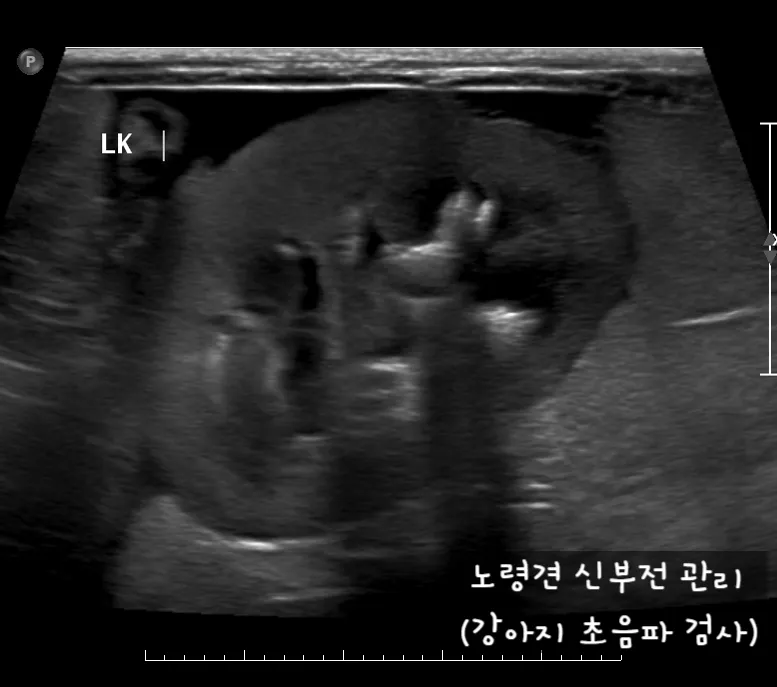

노령견 신부전2기 자연식 화식 레시피 건강식

노령견 신부전2기 화식 자연식 관리법

IRIS(International Renal Interest Society, 국제 신장 학회)에 따르면, 강아지 신부전은 1기부터 4기까지 총 4단계로 나뉘어 있습니다. 2기는 신장 기능이 매우 소폭 저하되어 큰 증상이 없는 단계예요.